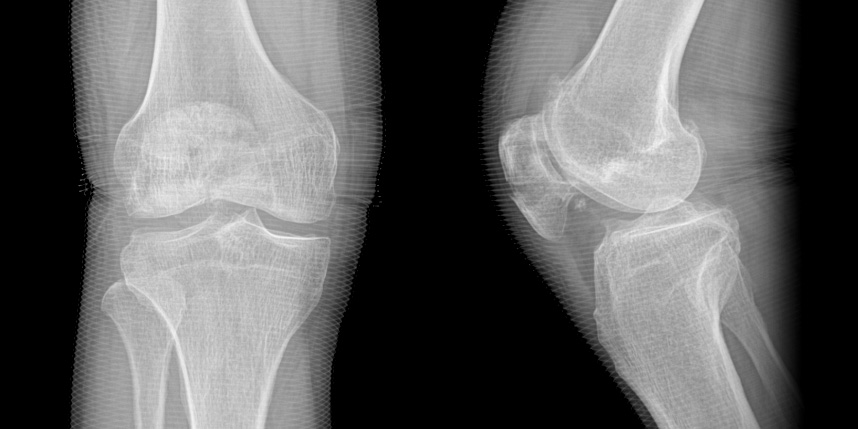

무릎 골절

골절은 정확하게 골절편을 잘 맞추고 고정하는 것이 중요합니다. 특히 관절면을 잘 맞추는 것이 중요합니다.

골절이 심하지 않은 경우에는 깁스로 고정해서 유합을 시킬 수 있으나, 정도가 심한 경우에는 손,발목 골절 수술을 진행할 수 있습니다.